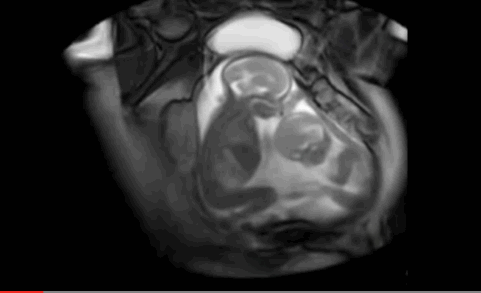

一开始小baby连续出招

大baby不为所动

接着小baby加猛攻势

大baby开始有所回应